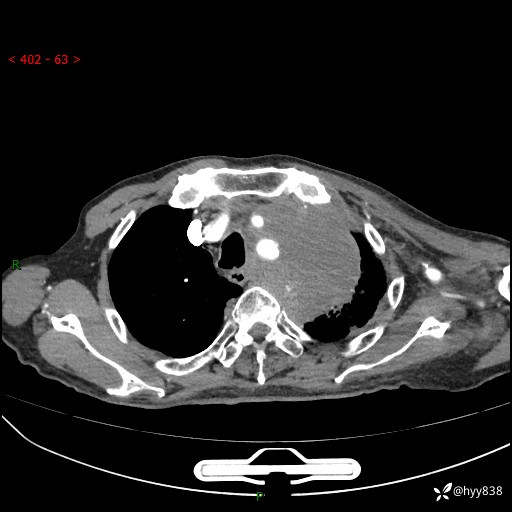

老年男性,气促5月,胸背痛2月。发现肺尖较大肿块,摧枯拉朽之势---结果公布~

现病史:患者于5月前饮酒后突发静息状态下气促不适,无胸闷、胸痛、发热、咳嗽、咳痰等不适,于当地第五人民医院及我院就诊,输液治疗后(具体不详)后气促稍缓解,遂出院后自行口服中草药治疗。近2月出现胸背痛,伴左上肢疼痛、乏力、感觉异常,稍有咳嗽、咳痰,咳黄痰、痰液粘稠,无咳血。为进一步诊治来我院。

胸部CT增强扫描(外院平扫)